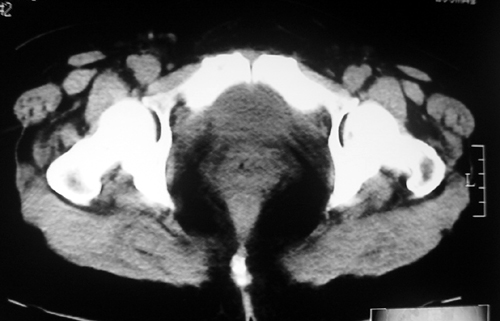

以下是引用余辉在2009-2-14 8:37:00的发言:[br]宫颈左后壁见较大低密度肿物影且向左后上方突出,宫腔内见大片状低密度区,考虑宫颈肿瘤,宫颈癌可能性大,伴宫腔积液或转移